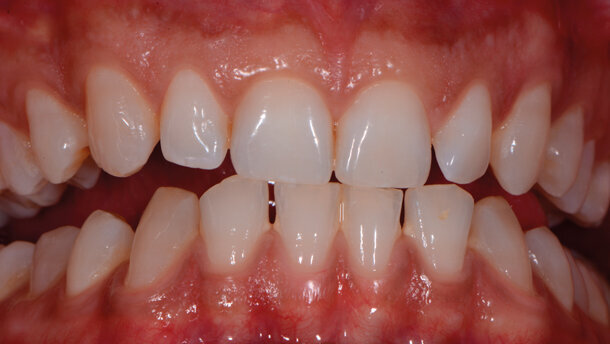

Case report Un paziente di anni 29 di sesso maschile si presenta per un controllo. In apparente salute sistemica, riferisce di avere bisogno di mostrare un sorriso luminoso e bianco poiché, essendo un odontoiatra, ha deciso di dedicarsi alla pratica clinica quasi esclusivamente estetica e cosmestica, comprese le tecniche di antiagening periorali (fotoringiovanimento e filler), e vuole valorizzare nei confronti dei suoi pazienti il suo aspetto curato e il sorriso smagliante, a mo’ di modello per corretti stili di salute orale; essere quindi testimonial esso stesso dell’efficacia delle terapie proposte.